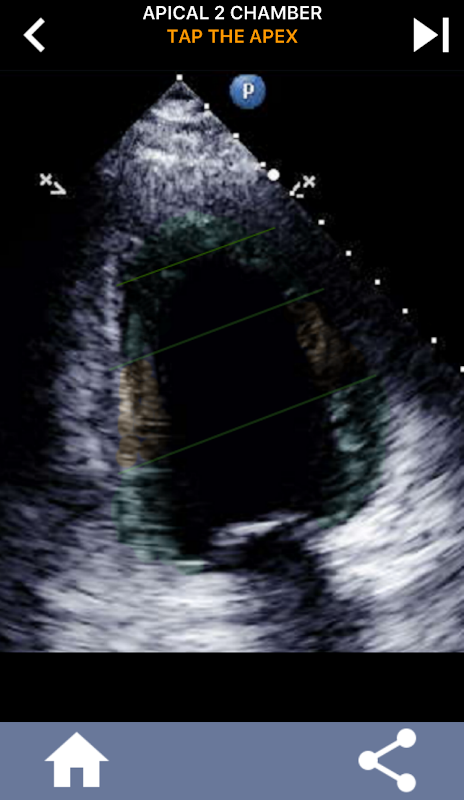

Cepat belajar AHA 17 segmen Model jantung, penting untuk SEMUA gema siswa!

Sangat penting bagi para ahli ultrasound untuk mempelajari segmentasi jantung American Heart Association dari ventrikel kiri menjadi 17 segmen yang merupakan standar yang banyak digunakan oleh banyak modalitas pencitraan lainnya seperti pencitraan resonansi magnetik, tes nuklir jantung, dll ... untuk menggambarkan lokasi segmen dan fungsi yang terpengaruh. Sering kali orang yang membaca gema Anda akan bertanya "apa yang Anda lihat?" dan membalas dengan lokasi yang tepat dari daerah yang terkena dampak adalah apa yang diharapkan.

Aplikasi ini berisi semua tampilan gema yang menunjukkan miokardium tersegmentasi AHA dan akan menanyai Anda untuk mengetuk segmen yang benar. Secara pribadi saya menemukan bahwa kuis berulang berulang paling baik untuk saya ketika saya perlu cepat belajar / menghafal subjek. Jika Anda seorang siswa ultrasound yang mempelajari echo / TTE saya pikir ini akan menjadi pelengkap yang sangat baik untuk studi Anda.